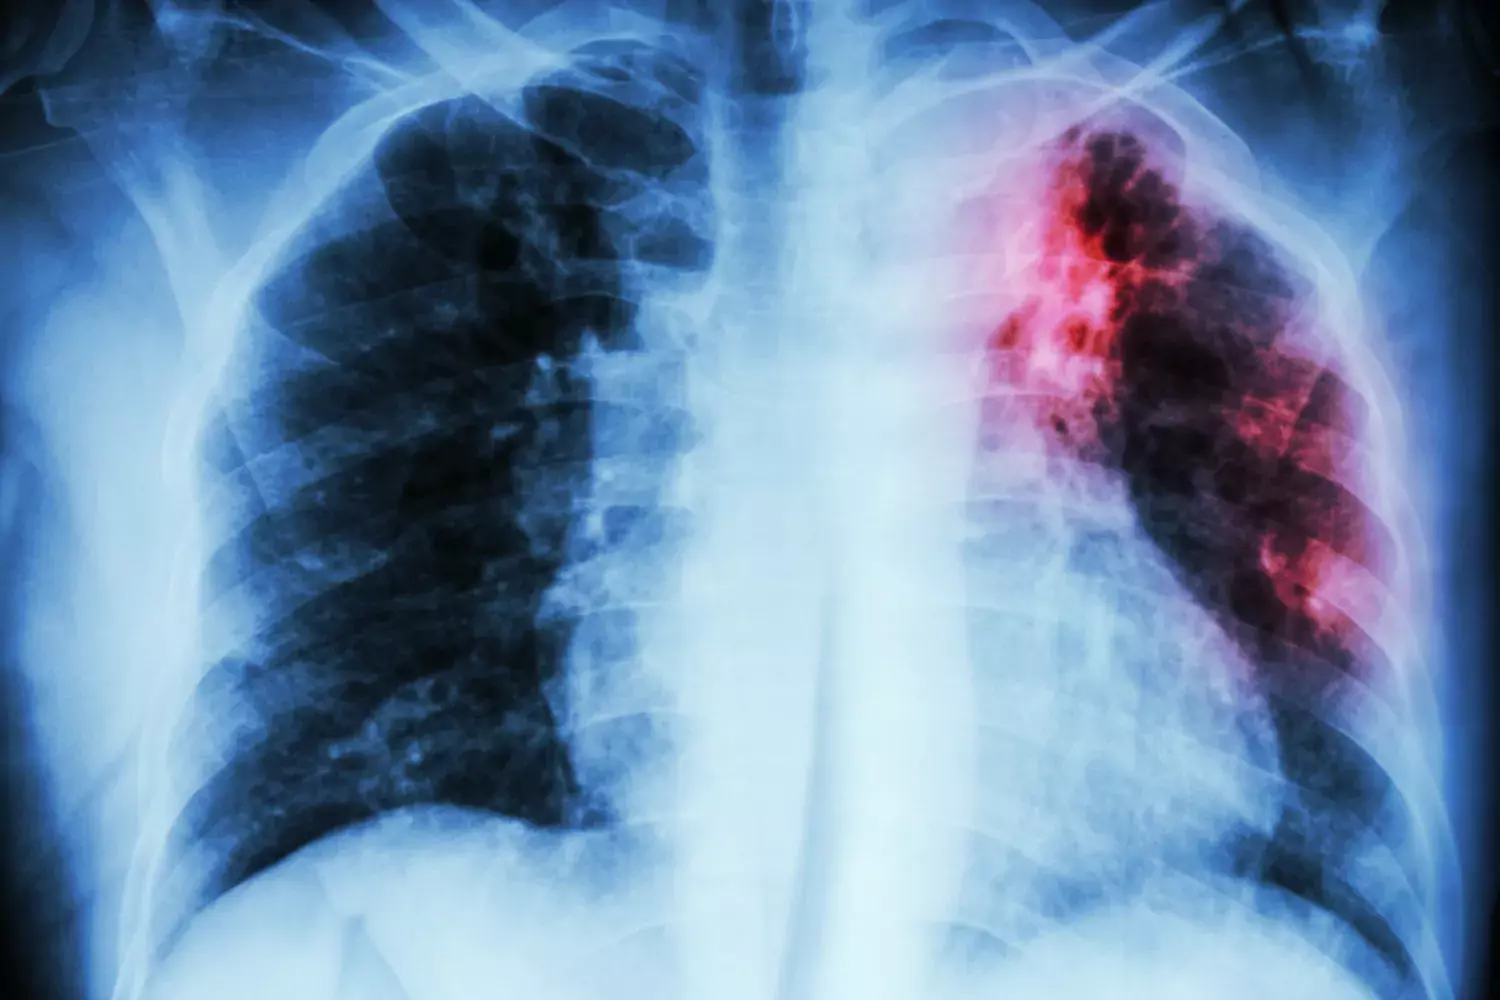

Angriper lungorna

Tuberkulos, eller TBC, är en infektionssjukdom orsakad av bakterier ur mycobakterie-släktet, i huvudsak Mycobacterium tuberculosis. Den vanligaste formen angriper lungorna, men sjukdomen kan ta sig olika uttryck och sätta sig i lymfsystemet, ryggraden, hjärnan och andra organ i kroppen.

Lungtuberkulos är den smittsamma formen som orsakar den stora spridningen när de sjuka hostar och nyser ut bakterier i små aerosoldroppar i luften. Det kan räcka med att andas in ett fåtal av dessa droppar för att bli smittad, men oftast krävs mer långvarig och nära kontakt. Immunförsvaret hos nio av tio smittade klarar dock att döda eller kapsla in bakterierna i så kallade granulom och oskadliggöra dem, vilket innebär att de inte får några sjukdomssymtom.